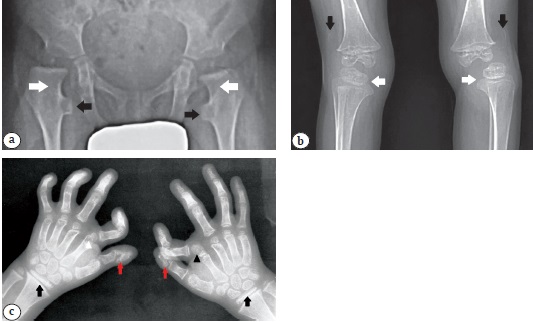

На рентгенограммах тазобедренных суставов обращают на себя внимание широкие и короткие шейки бедренных костей с типичной формой проксимального отдела бедренной кости в переднезадней проекции. Проксимальные зоны роста бедренной кости ориентированы горизонтально. Рентгенограммы коленных суставов выявили ротационные вывихи костей голеней и вывих надколенника (рис. 2 а). На рентгенограммах позвоночника: выраженный правосторонний поясничный сколиоз (рис. 2 b). На рентгенограмме верхней конечности выявлены варусная деформация проксимального отдела плечевой кости, подвывих головки лучевой кости (рис. 2 c). На рентгенограммах кистей обнаружены характерные изменения, включающие локтевую девиацию кисти вследствие деформации суставной поверхности дистального отдела лучевой кости, короткие вторые пястные кости, мозаично распределенные конусовидные деформации и уплотненные по типу «слоновой кости» эпифизы пястных костей и фаланг пальцев. Характерная экстрафаланга вторых пальцев была отделена от второй пястной кости и основной фаланги слева и сливалась с фалангой справа, отмечено типичное раздвоение дистальной фаланги большого пальца (рис. 2 d).

Рис. 2. Рентгенограммы пробанда 1:a — нижних конечностей в прямой проекции: форма шейки бедренной кости по типу «гаечного ключа» (белые стрелки); ротационный вывих костей голени — дистальный отдел бедренной кости отражен в прямой проекции (отмечено белым кругом), проксимальный отдел большеберцовой кости — в боковой проекции (отмечено чёрным кругом); вывих надколенника (черная стрелка);b — позвоночника в прямой проекции: тяжелый правосторонний поясничный сколиоз (белая стрелка);c — верхней конечности: варусная деформация проксимального отдела плечевой кости (белая стрелка), подвывих головки лучевой кости (черная стрелка);d — кистей в прямой проекции: локтевая девиация вследствие отклонения дистальной суставной поверхности лучевой кости (белые стрелки); короткие вторые пястные кости (черные стрелки); экстрафаланга второго пальца отделена от второй пястной кости и основной фаланги слева (черный треугольник) и сливается с основной фалангой справа (белый треугольник), раздвоенная дистальная фаланга большого пальца (красная стрелка)

На рентгенограммах тазобедренных суставов выявлены типичные деформации проксимальных отделов бедер в виде «гаечного ключа» вследствие визуально широких и коротких шеек бедренных костей в сочетании с удлиненным малым вертелом (рис. 4 а). На рентгенограммах коленных суставов: ротационный вывих костей голени и вывих надколенника (рис. 4 b).

На рентгенограммах кистей рук выявлены уплощенные эпифизы дистального отдела лучевой кости, мозаичные конусовидные эпифизы пястных костей и фаланг, экстрафаланги вторых пальцев (отделена от второй пястной и базальной фаланги слева и срослась с фалангой справа), раздвоенная дистальная фаланга большого пальца; опережающая оссификация костей запястья (рис. 4 с).

Рис. 4. Рентгенограммы пробанда 2:а — тазобедренных суставов в прямой проекции: проксимальный отдел бедренной кости деформирован по типу «гаечного ключа» (белые стрелки), удлиненный малый вертел (черные стрелки); b — коленных суставов в прямой проекции: ротационный вывих костей голени (белые стрелки) и вывих надколенника (черные стрелки);с — кистей в прямой проекции: уплощенные эпифизы дистального отдела лучевой кости (белые стрелки); экстрафаланга второго пальца сливается с основной фалангой второй пястной кости слева (белый треугольник) и отделяются от фаланги справа (черный треугольник); раздвоенная дистальная фаланга большого пальца (красная стрелка)